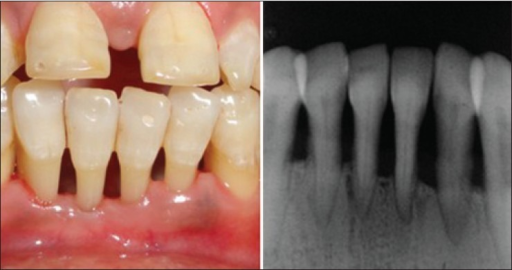

Gingival recession is displacement of the soft tissue margin apically leading to root surface exposure.

Intra-oral examination revealed scar tissue extending onto the attached gingivae associated with a mobile upper right central incisor together with marked gingival recession on the mesial aspect of 12.